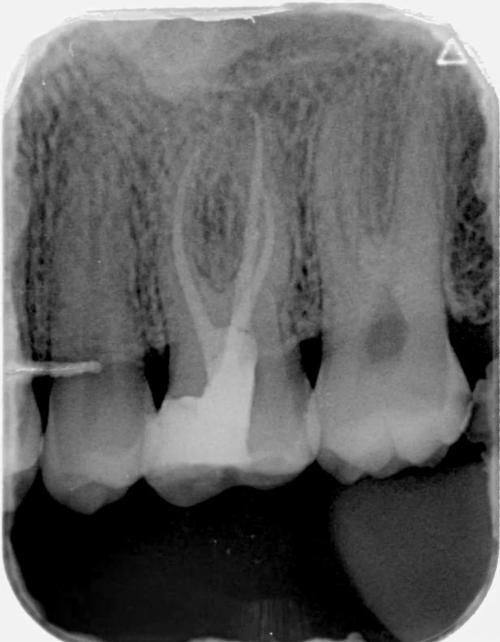

根管治疗:能够精细处理牙髓病变问题,保留患牙,有效缓解牙痛症状,操作细致严谨,尽可能减少治疗过程中的不适感。